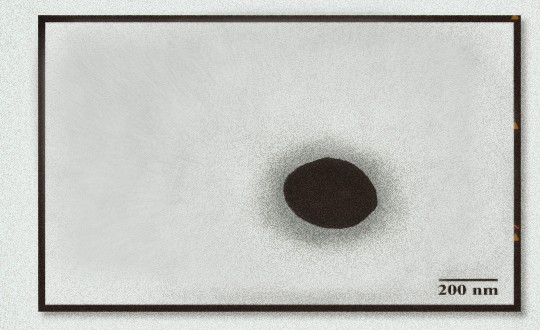

Fig. 3: Phytosome morphology using Transmission Electron Microscope (TEM) with a magnification of 30,000x for phytosome formula with 1:0.5 ratio (F1)

Phytosome morphological analysis using Transmission Electron Microscope (TEM) displayed irregular spherical vesicles measuring 200 nm (fig. 3) for phytosomes with the 1:0.5 ratio.